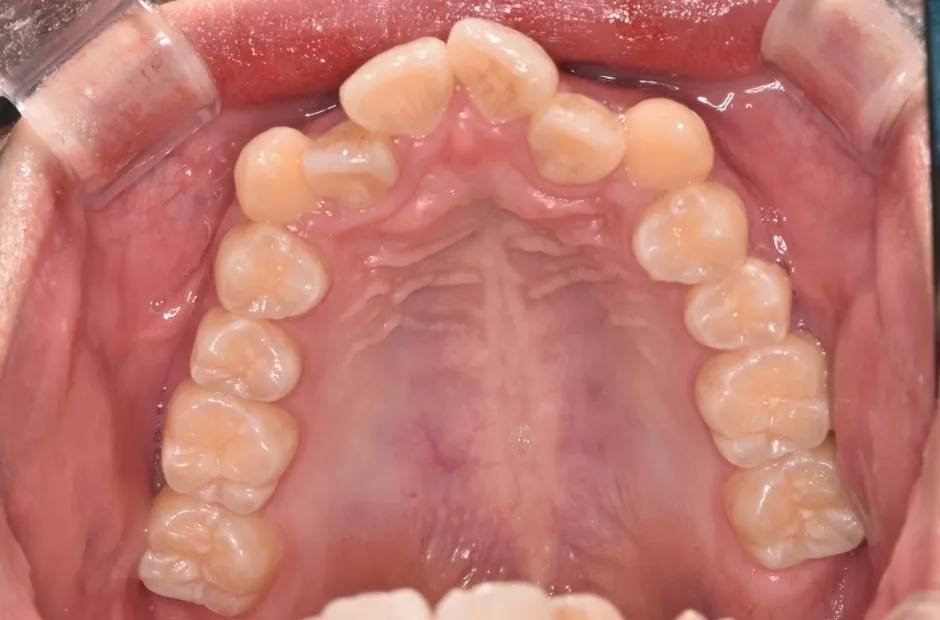

治療症例

ブラケット矯正

前歯部反対咬合

| 診断名・主訴 | 前歯部反対咬合 |

|---|---|

| 年齢・性別 | 14歳・男性 |

| 治療期間・回数 | 1年2か月 |

| 治療に用いた主な装置 | ブラケット矯正 |

| 抜歯部位 | なし |

| 治療費 | 60万円(税抜) |

| リスク・副作用 | 装置による違和感・疼痛・歯肉退縮・歯根吸収・虫歯のリスクなど |

治療前

治療後